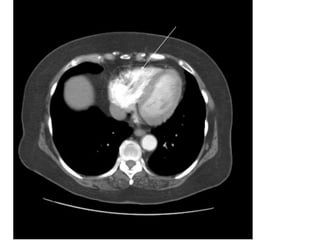

VỠ LOÉT ĐỘNG MẠCH CHỦ NGỰC

-> MÁU XOANG NGỰC (T)